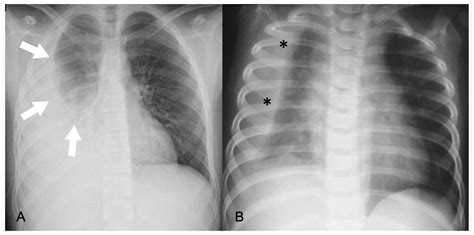

• Chest X-ray: Imaging the lungs to detect inflammation, fluid buildup, or consolidation.

A premature infant born at 28 weeks gestation developed pneumonia at three weeks of age. The infant was admitted to the neonatal intensive care unit (NICU) with symptoms of rapid breathing, fever, and lethargy. A chest X-ray confirmed the diagnosis of pneumonia, and the infant was treated with antibiotics and supportive care. After a two-week hospital stay, the infant recovered and was discharged home with close follow-up.